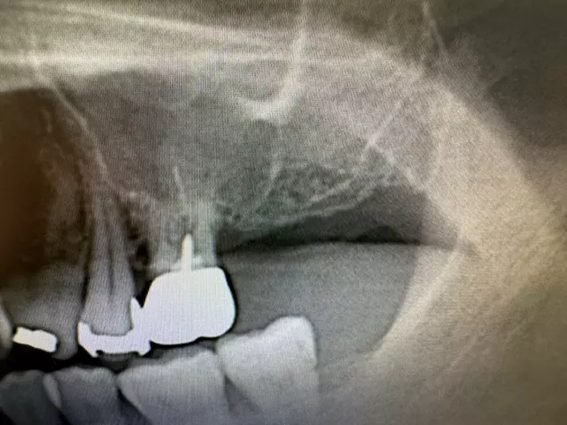

| 主訴 | インプラント 左上6番7番部 インプラント埋入 |

| 治療内容 | 左上6番7番部インプラント埋入。 左上6番部 上顎洞まで約1.5㎜。 左上6番 抜歯即時埋入。 左上7番 もともと歯が無かったため、通常埋入。 |

上顎洞へ突き抜けているように見えますが、抜歯窩への埋入のため、実際は抜けていません。